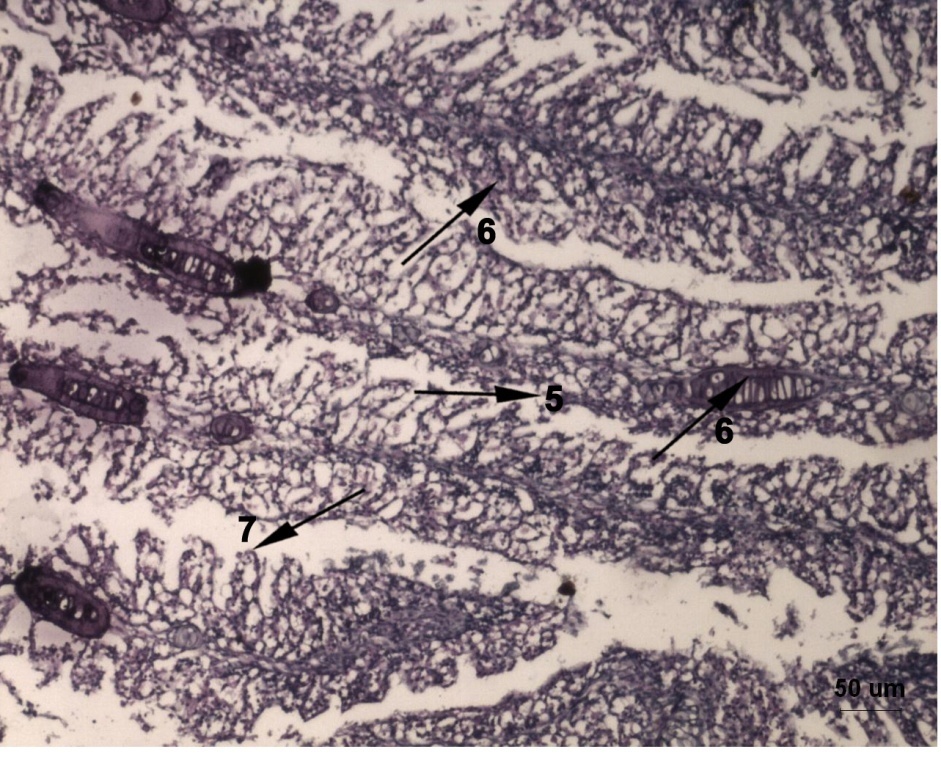

Fig. 2: Histological alterations of gills of Labeo rohita fish exposed to lead acetate and fed with normal fish food stained with Hematoxylin and Eosin showing swollen gills. 1-Thickening of Cartiligous rod, 2-Edema, 3-Hyperplasia, 4-Shorter Secondary Lamella, 5-Hypertropy. Scale Bar = 50 µm

Fig. 3: Histological alterations of gills of Labeo rohita fish exposed to lead acetate and fed with normal fish food stained with Hematoxylin and Eosin showing 5-Fusion of Secondary Lamella, 6-Disappearance of Inter Lamellar Space, 7-Degeneration of Primary Filaments. Scale Bar = 20 µm

The gill of lead acetate exposed fish, fed with normal food (fig. 1b & fig. 1c) showed remarkable histopathological lesions like thickening of the supporting cartilaginous rods and hyperplasia of the epithelial cells that caused fusion of adjacent secondary gill lamellae. In addition, the secondary lamellae became shorter and lamellar fusion formed lumps. Further, edema between the primary epithelium and secondary lamella, severe degeneration with fibrosis in primary filaments and disappearance of inter lamellar spaces (ILS), were also observed. The gill of lead acetate exposed fish fed with supplementary food (fig. 1d) expressed apparently normal architecture of control fish.